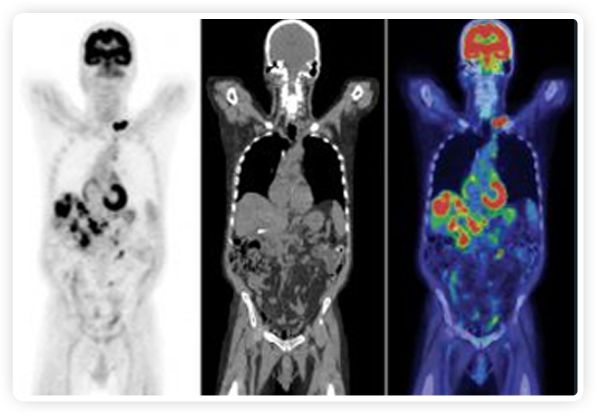

正電子發(fā)射斷層掃描(PET)是癌癥檢測中已建立的成像標(biāo)準(zhǔn),與其他成像方式相比,PET能提供高靈敏度和特異性的圖像。

到目前為止,放射腫瘤學(xué)中(使用的圖像主要是結(jié)構(gòu)性的,而PET圖像可以提供生物學(xué)信息。通過使用注射示蹤劑,例如18-FDG,PET可以描繪腫瘤的代謝活性,使其“點亮”。(FDG是用于可視化癌癥代謝的最廣泛使用的示蹤劑。與正常組織相比,腫瘤細(xì)胞保留更高水平的FDG。)不同的PET示蹤劑可以識別腫瘤的不同生物學(xué)特征,例如特定生物標(biāo)志物抗原(例如,PSMA)或甚至探測免疫系統(tǒng)本身(例如,PDL1表達(dá)或活化的T細(xì)胞)。